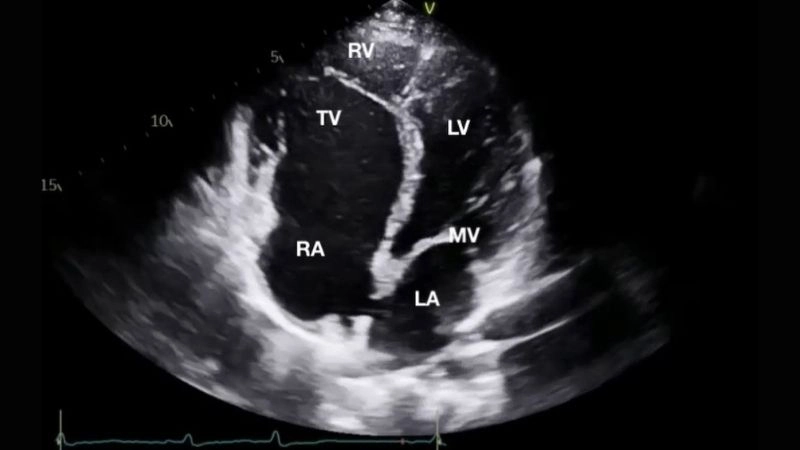

Images visual examples of Ebstein's anomaly

Ebstein's anomaly is a rare congenital heart defect where the tricuspid valve is malformed, causing improper blood flow between the right atrium and right ventricle.